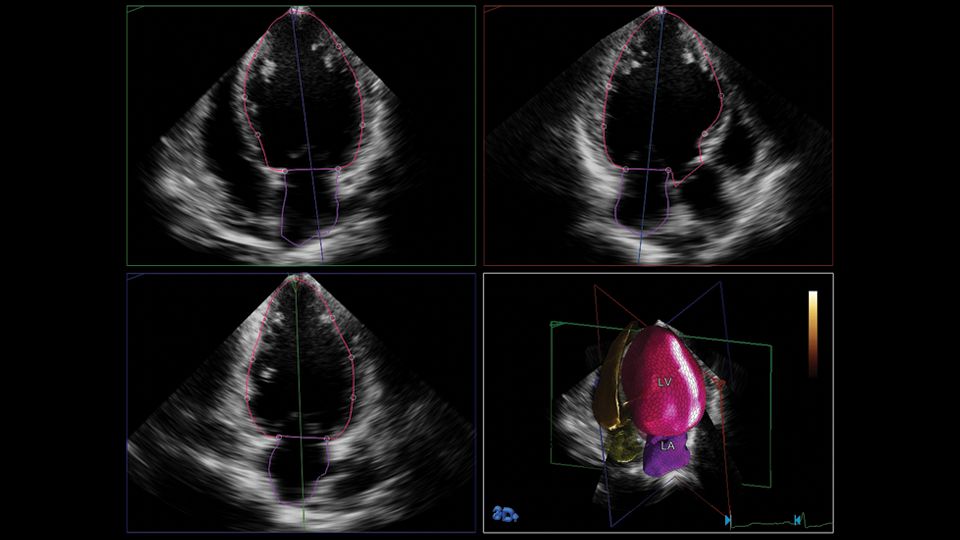

HeartModel clinical image

Philips has recently developed HeartModel, a fully automated 3D-TTE analysis software which simultaneously detects LA and LV endocardial surfaces throughout the cardiac cycle, using an adaptive analytics algorithm that consists of knowledge-based identification of initial global shape and orientation followed by patient specific adaptation (Figure 1). The process begins with the program estimating the LV end-diastolic (ED) frame using motion analysis near the peak of the electrocardiographic R-wave. Using this frame, general shape orientation is identified, and then the LV end-systolic (ES) frame is estimated using motion analysis to identify the smallest LV cavity. Once LV ED and ES frames have been estimated, preliminary ES and ED models of the LV and LA are built using the automatically detected endocardial surface in conjunction with information from a 3D TTE LA and LV database. This database consists of a variety of LA and LV ED and ES shapes obtained from approximately 1,000 3D-TTE data of varying image quality in patients with a wide range of chamber size and function. The program matches features from the LV volume being analyzed to selected shapes in the database. This selected shape is then locally adapted to the LV volume under study using a series of incremental steps. The ED and ES frames are then finally detected by evaluating the LV volumes in the neighborhood of end-diastole and end-systole and selecting the frame with the maximum and minimum volumes, respectively. The algorithm was designed to adjust to a variety of imaging conditions, including variations in dropout, acoustic clutter, ventricular shape and cardiac orientation relative to the transducer. However, similar to manual measurements, a minimum number of visible endocardial border segments (~14-15 of 17 LV segments) is necessary for an accurate estimate of the chamber volume to be derived. Lastly, when run on the same data set, the algorithm has a deterministic convergence response, thus yielding zero variability. Once the final model has been fitted, the LA and LV contours are displayed on 2D cut-planes derived from the 3DE data sets showing the ES and ED 4-, 3- and 2-chamber views (Figure 2). If the user is not satisfied with the LA and LV contours, they could be manually edited.

Figure 2